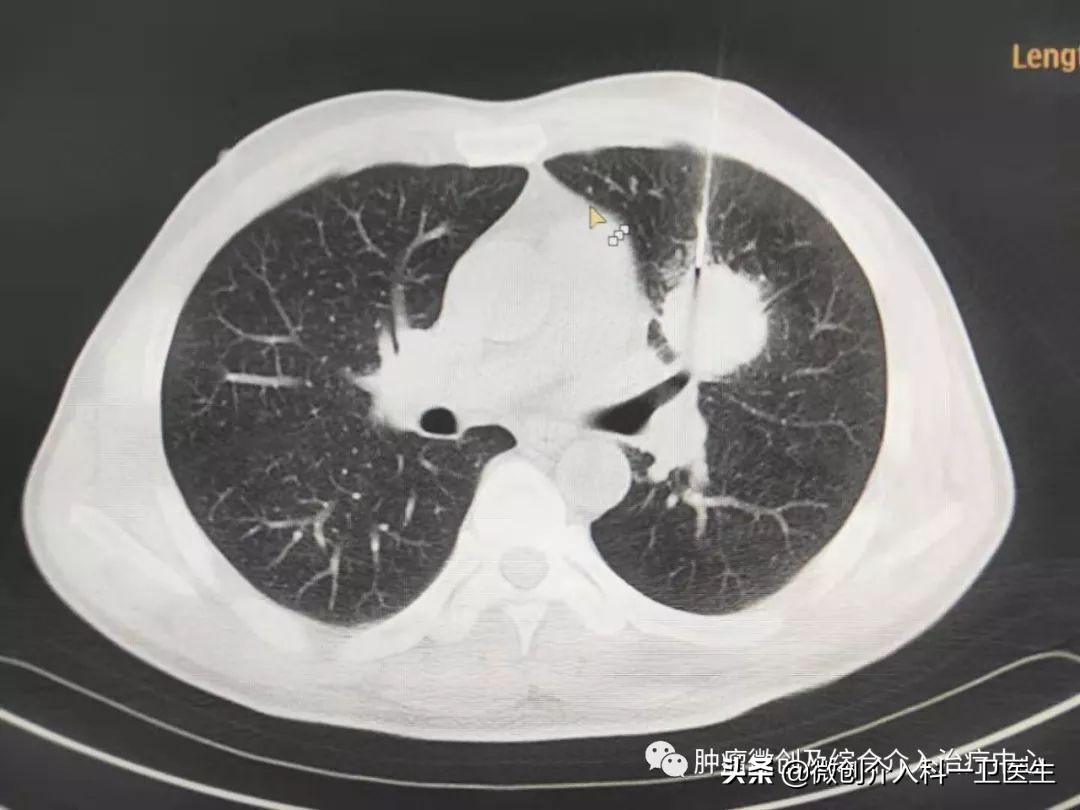

图 3. CT引导下穿刺过程。

图1、2 局麻后在CT精确引导下经穿刺活检针穿刺进入肿瘤内部,创口约棉签样大小,取出长条形软组织,进行病理化验。